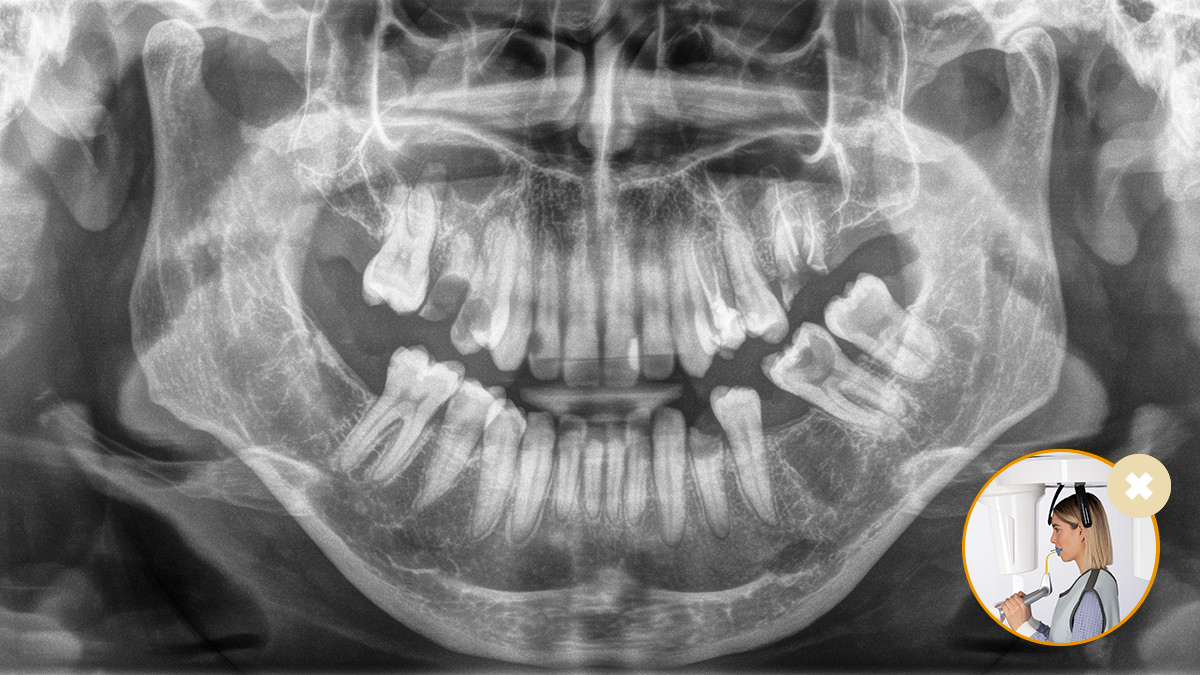

Correct patient positioning leads to high image quality to support an accurate diagnosis and facilitates and improves patient experience.

This is our 10-point concept for easy patient positioning and X-ray imaging. It is primarily about two things: high image quality and comfort for the patient and the assistant.